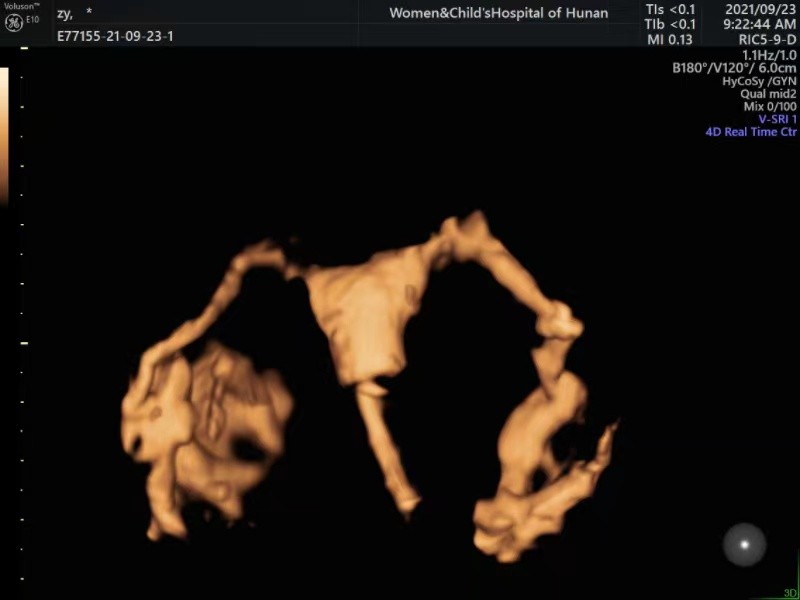

是 利用造影剂微气泡在超声下显影成像的特点 ,利用导管向 子宫腔注入超声造影剂 ,在超声下动态 观察造影剂经过宫腔、输卵管时,子宫输卵管的显影形态及伞端造影剂溢出流入盆腔后的分布情况, 来判断 宫腔形态 ,确定有无 子宫畸形 、 宫腔粘连、子宫黏膜下肌瘤、子宫内膜息肉及异物等 ,及评价输卵管内 通畅性的检查

方法。